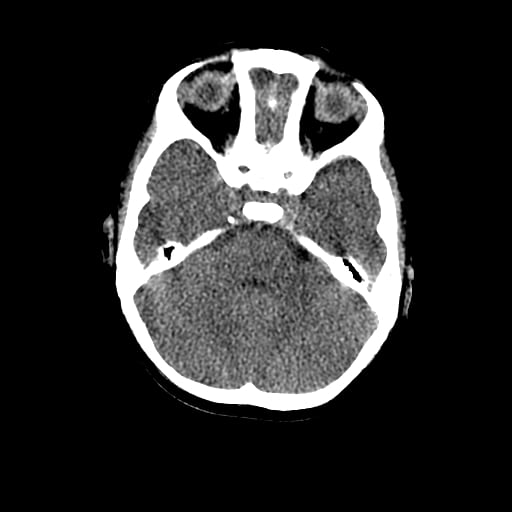

Age: 1

Sex: Male

Indication: Fall